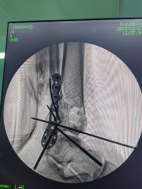

控制機器人牽引斷端,可見關(guān)節(jié)間隙恢復。

外側(cè)切口放置鋼板,固定腓骨。

穿針輔助復位脛骨遠端骨折塊,安裝內(nèi)固定